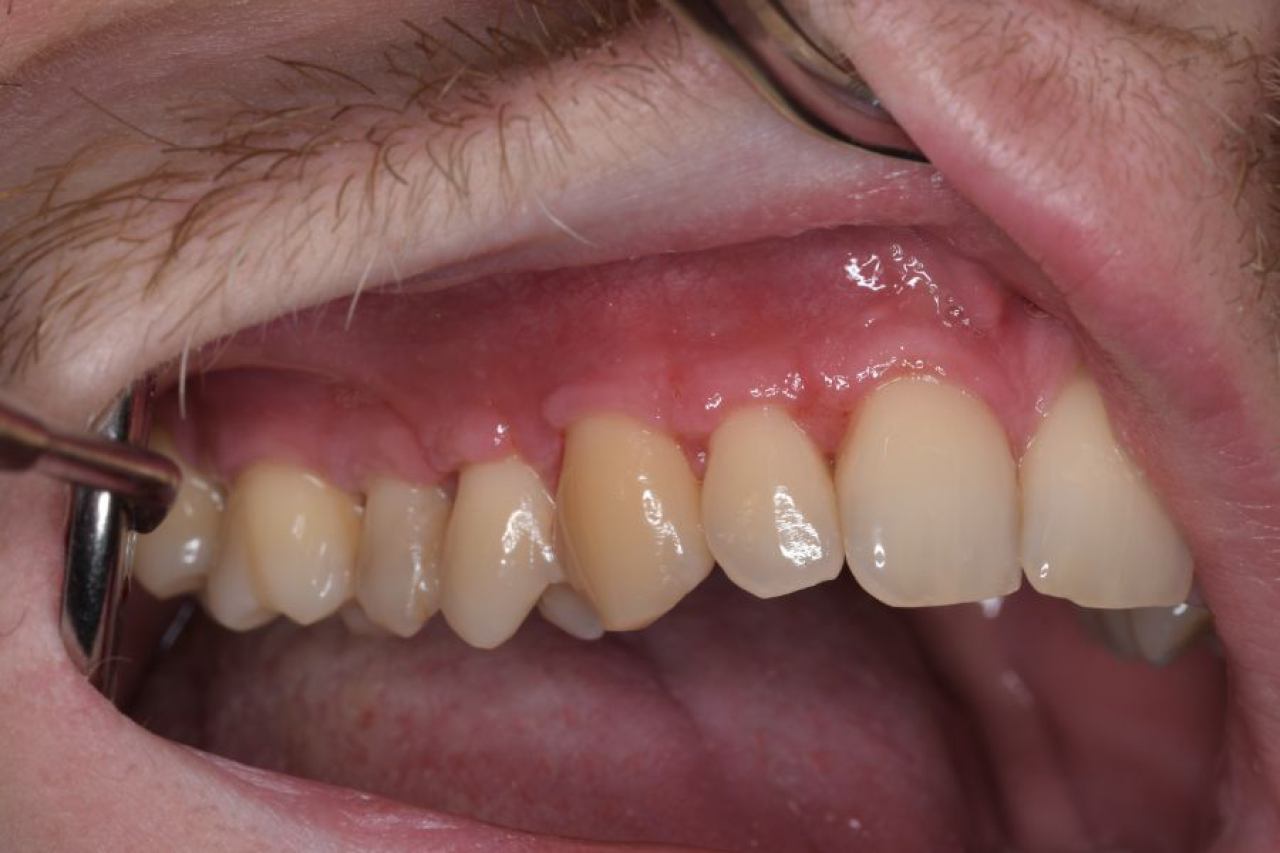

Parodontologija i kirurgija

Parodontologija je grana dentalne medicine koja se bavi zdravljem potpornih struktura zuba (parodonta). Parodont se sastoji od zubnog mesa (gingiva), kosti i vlakana koja vežu zub za kost (parodontalni ligament).

Ovo je grana kojoj Marković Dental Clinic pridaje puno pažnje jer je vrlo kompleksna i bitna za cijelo oralno zdravlje.

Regeneracija kosti i mekog tkiva

Gingivalne recesije u narodu poznatije kao „povlačenje zubnog mesa" moguće je korigirati kirurškim zahvatom te vratiti gingivu (zubno meso) u fiziološki položaj mikrokirurškim tehnikama. Zahvati koje odrađujemo kod regeneracije kosti i mekog tkiva su podizanje dna sinusa (sinus lift) i nadomještanje izgubljenog volumena kosti (augmentacija kosti, regeneracija kosti).